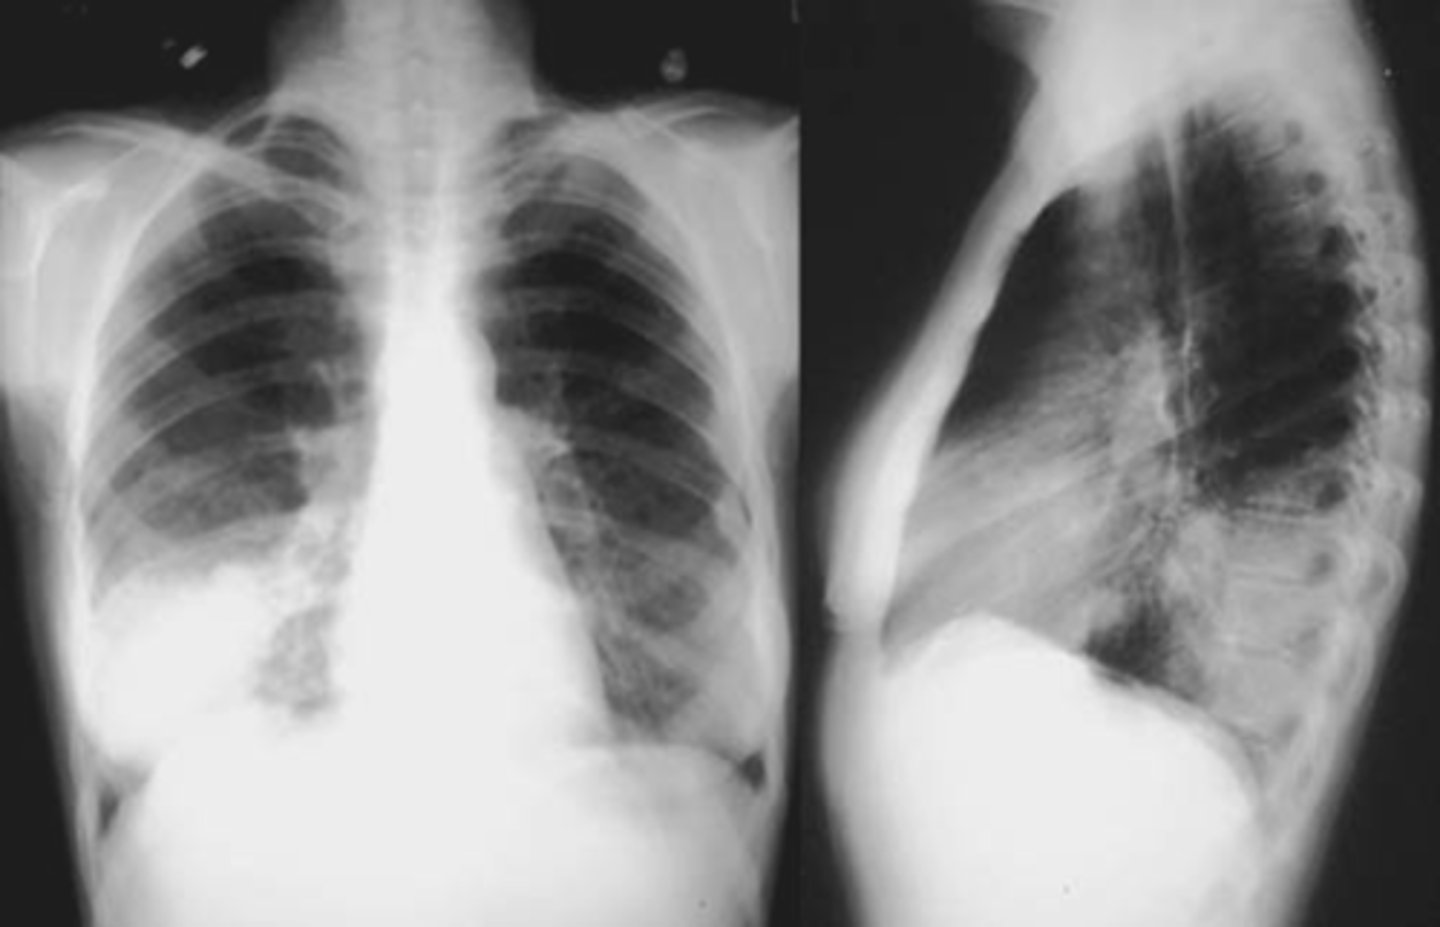

Reticular interstitial infiltrate (fine)

Reticular interstitial infiltrate (coarse)

Nodular Interstital infiltrate

Reticulonodular interstitial infiltrate

CAP- interstitial